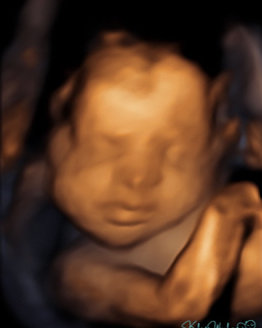

Our excitement and anticipation for Luna led us to document every stage she goes through. At 12 weeks you can see our angel was almost the size of a lime... Then, at 20 weeks, she grew into a good-sized fig. Upon arriving, our Luna will hopefully be the fully-grown Melon she’s meant to be! You can check out her journey here. We want everyone to be part of the amazing ride we are going through!